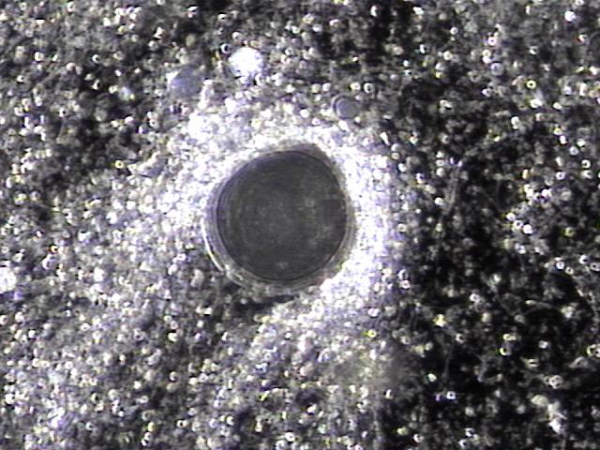

내원 첫날 전립선의 표적 치료후 막혀 있던 사정관과 정낭등의 결석이 배출되고 혈정액등이 치료되고 있는 현미경학적 자료입니다.

This is a microscopic image taken after the first targeted prostate treatment on the day of the initial visit, showing the discharge of calculi that had been blocking the ejaculatory ducts and seminal vesicles, as well as the treatment of hemospermia and related findings.![]()

This is a microscopic image taken after the first targeted prostate treatment on the day of the initial visit, showing the discharge of calculi that had been blocking the ejaculatory ducts and seminal vesicles, as well as the treatment of hemospermia and related findings.